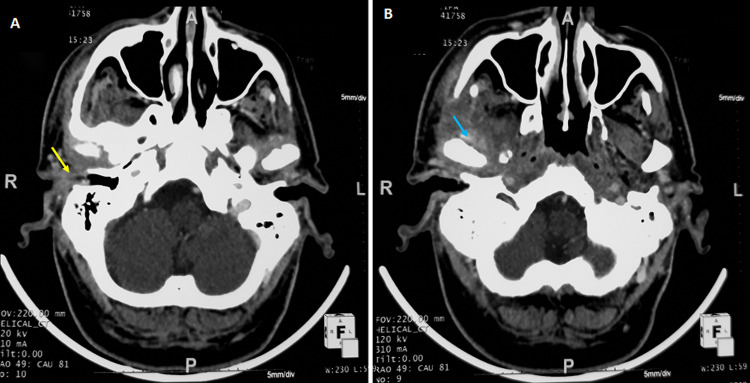

Fungal necrotizing external otitis (NEO) is a rare disease. It is an aggressive and potentially fatal infection. The most commonly reported pathogen is Candida. We aim through this study to share our experience in the management of fungal necrotizing external otitis and discuss its diagnosis tools, anti-fungal treatment choice, and outcomes. We included fifteen patients with diagnosis criteria of fungal NEO; clinical features of NEO with positive culture swabs and/or positive serologic test to a fungal pathogen. The mean age was of 70 years with a prevalence of males. The main symptoms were otalgia (n=15) and otorrhea (n=7). Facial palsy was observed in four cases. Fungal pathogens were Candida(n=10) and Aspergillus (n=5). Complications were observed in eight cases: extension to the temporo-mandibular (n=4), abscess in the retropharyngeal space (n=2), abscess in the parapharyngeal space (n=1) and thrombophlebitis of the internal jugular vein (n=1). Six patients were treated with fluconazole, eight with voriconazole, and one patient with itraconazole. After a mean duration of 52 days of antifungal therapy, fourteen patients have been cured with normalization of the ear symptoms, biological, and imaging features. One patient died of septic shock. No recurrence of the disease was observed after a follow-up of 12 months in all cases.